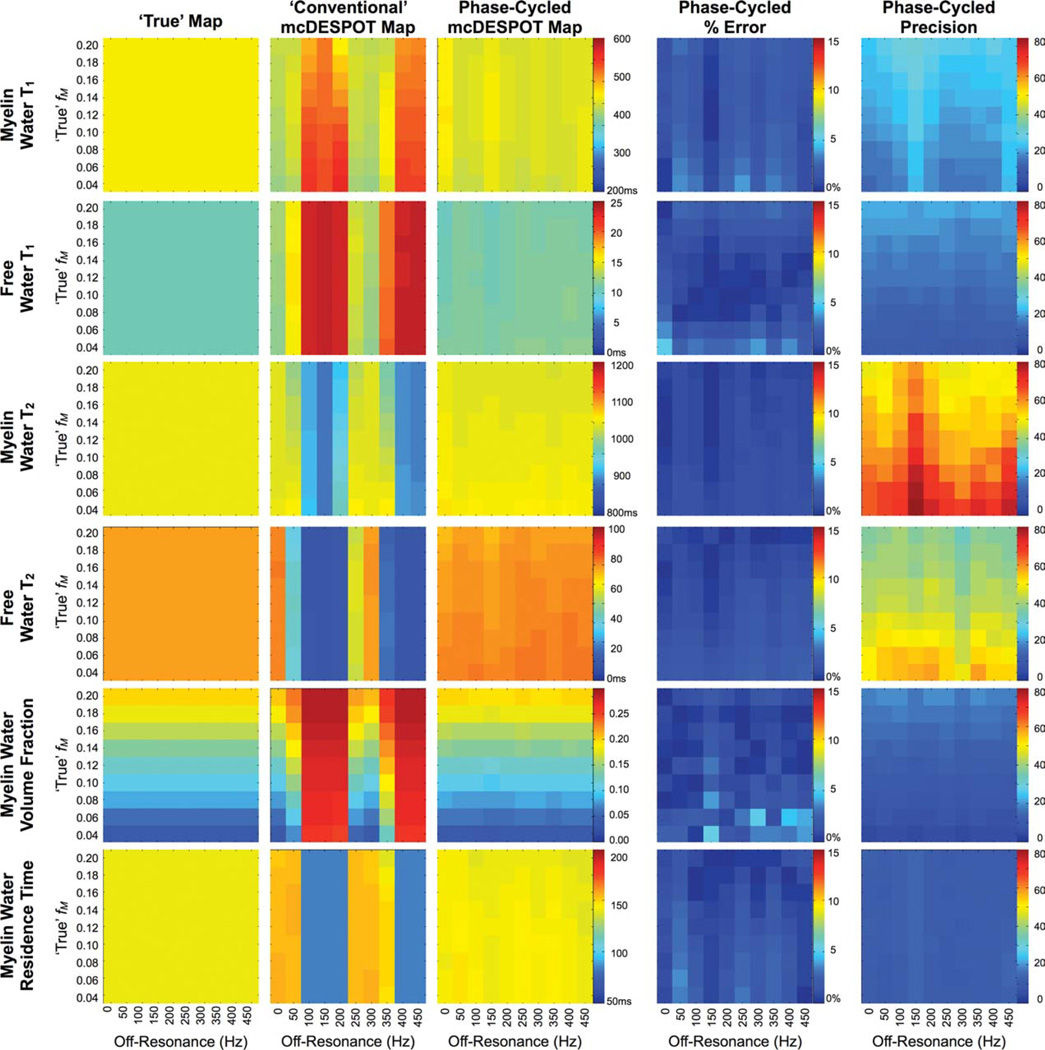

Results of the RF phase-cycling simulations are shown in Figs. 7 and 8, which show corrected and uncorrected T1,M, T1,F, T2,M, T2,F, fM, and tM estimates over a range of myelin water volume fraction and off-resonance values. The sensitivity of mcDESPOT to off-resonance is visually demonstrated in Figs. 7 and 8. The uncorrected estimates show significant deviation from the true theoretical values at even subtle δω. The inclusion of off-resonance modeling significantly improves the accuracy of the derived parameter estimates, with less than 5% absolute error observed in each of the parameters across the investigated myelin fraction and off-resonance values.

FIG. 8.

Simulation results of the accuracy and precision of off-resonance corrected myelin water volume fraction estimates. Error in the derived estimates was less than 5%.

Figure 10 displays maps of each of the six mcDESPOT parameters (T1,M, T1,F, T2,M, T2,F, fM, and τM) calculated without B0 or B1 correction; with only B0 correction; and with both B0 and B1 correction. As observed in Fig. 8, these data exemplify the B0 and B1-related errors in each of the multicomponent parameters and demonstrate the corrective ability of the presented flip angle and off-resonance modeling techniques. In general, it is noted that flip angle errors appear to predominately affect the T1 measures, whereas off-resonance principally influence the T2 measures. However, both have significant influence on the derived myelin water fraction estimates.

Axially reformatted through each of the mcDESPOT parameter maps calculated without any correction; with only B0 correction; and with B0 and B1 correction. As shown in the simulations, both B0 and B1 inhomogeneity result in widespread error in each of the multicomponent parameters. These areas of artifact are significantly improved in the corrected images.

In Fig. 11, we show axially reformatted images through the uncorrected; B0 only; and fully B0 and B1 corrected myelin water volume fractions maps at different levels throughout the brain. Again, these images demonstrate not only the severity of artifact in the uncorrected maps but also their effective removal and elimination when B0 and B1 are modeled and appropriately accounted for.